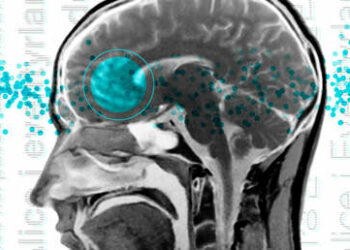

Científicos descubren la molécula que da origen al miedo en el cerebro

Un equipo internacional de investigadores publicó este martes en la revista Cell Reports un estudio en el que revelan haber ...